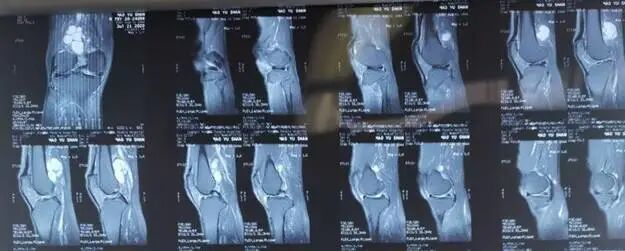

除了患者的症状及体征外,临床上腘窝囊肿的诊断通常还需要通过影像学检查来确定。X线检查通常无法显示囊肿,但可以排除其他病变。超声、CT和MRI可以帮助确定囊肿的位置、大小和形状,以及与周围组织的关系。

选择何种方式可依据术前核磁共振的检查情况决定。核磁共振显示腘窝囊肿与关节腔相通,腓肠肌间隔血管、神经的囊肿时建议的手术方式为前内外侧入路处理膝关节腔病变+单后内或双后内入路切除囊肿。如下图所示:

对于如何选择单后内或双后内入路切除囊肿,一可以通过术前膝关节核磁共振的检查了解囊肿的大小、位置及是否存在分隔来决定;二可以通过术中视野及操作决定;由于单后内入路切除术,观察入路位于前方,由于胫骨平台及内侧腓肠肌的遮挡,视野存在一定的盲区,对于囊肿相对较小,基本位于膝关节线水平、无分隔的囊肿,可以选择该入路进行手术;而对于囊肿较大、囊肿上下边界距离关节线比较远的囊肿,为了较好的将囊壁较完全的切除通常选择双后内入路切除囊肿。

腘窝囊肿是一种骨科十分常见的疾病。传统的开放手术创伤大、恢复慢、大多数因无法处理病根,复发率相对较高。关节镜手术可以做到切口小、恢复快,同时可以做到“标本兼治”,复发率低。术前检查膝关节MRI有重要意义:可以明确关节腔内的是否存在病变、了解囊肿是继发还是原发;可以明确手术的方式的选择;单后内入路:用于部分继发型腘窝囊肿,囊肿较小、无分隔的;优点:手术技术相对简单,较容易掌握;缺点:由于胫骨平台及腓肠肌等组织结构的遮挡,入路观察视野有限,对于较大的囊肿、分隔囊肿,囊壁难以切除完全。双后内入路:适用于所有继发型腘窝囊肿,但学习曲线相对较长,需要有较好的镜下空间立体结构感。